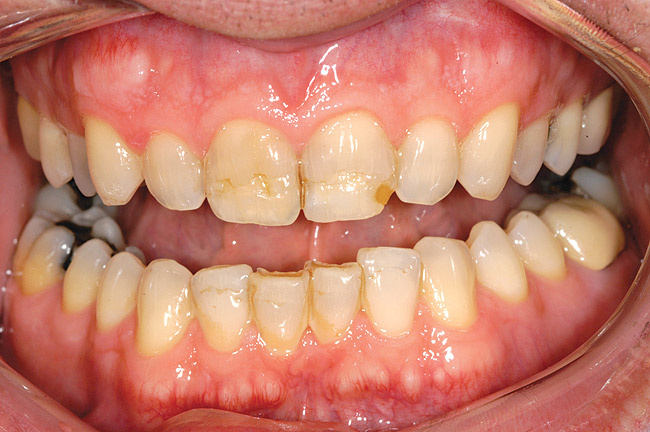

Figure 7a  Teeth Nos. 4, 5, and 30 were in need of indirect restorations and were treatment planned for all-porcelain, adhesively retained restorations.

Figure 7a

Figure 7b  A desire to increase the buccal contour of tooth No. 5 and the visibility of the maxillary bicuspids within the esthetic zone suggested that facial margins be placed at the free gingival margin.

Figure 7b

Figure 7c  Harmonious blending of indirect restorations and natural tooth structure provides improved esthetics and conservation of tooth structure.

Figure 7c

Figure 7d  Note that the facial margin was carried to the free gingival margin on the maxillary bicuspids. However, in areas of less esthetic significance, such as the tooth No. 30, the margin was kept supragingival in an effort to further conserve tooth structure.

Figure 7d

A chamfer finish line provides for the most esthetic blending of porcelain and tooth structure and is commonly added as the final detail to the facial aspect of the preparation (Figure 5). The occluso-cervical position of the facial chamfer is largely dependent on the need to alter tooth color. If the inherent color of the tooth is acceptable, a 2-mm chamfer is all that is required to blend the porcelain/tooth interface (Figure 6A through Figure 6E). A need to effect a color change dictates a facial finish line carried to the free gingival margin.

Additional indications for carrying the facial aspect of the preparation to the free gingival margin include the intent to alter the buccal contour of the tooth with the final restoration or the desire to eliminate the need for pre-existing Class V restorations (Figure 7A through Figure 7D). Ideally, the depth of the chamfer should be maintained within enamel to maximize bond strengths.34,35 Knife-edge margins should be avoided as they are not well-suited to all-porcelain restorations. To increase marginal fit, it is recommended that all sharp edges are eliminated and finishing burs are used to minimize surface roughness (Figure 8).36 Transitions from platforms created by the occlusal reduction and axial shoulders should likewise follow a smooth slope that avoids steep angles to the long axis of the tooth. To increase resistance to fracture under occlusal load, all transitions should be smooth and gradual.37 Sharp angles in the preparation are to be avoided, as they generate areas of high stress within porcelain. Smooth-butt margins, 90° to the cavosurface, are considered ideal.